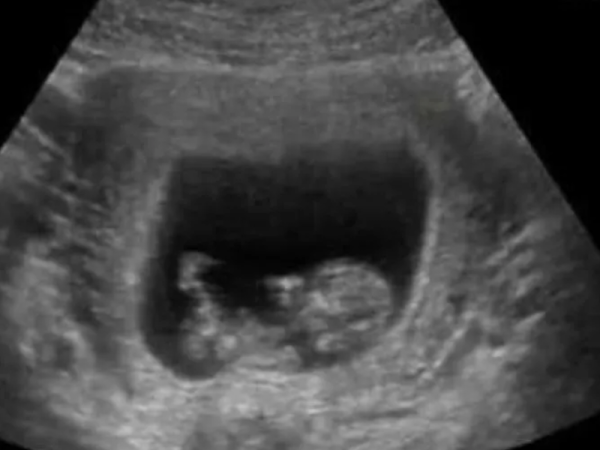

Cande Ruggeri le puso una condición particular a quienes visitan a su bebé recién nacida Camilo y Evaluna se cansaron y salieron a responder sobre los rumores que giraban en torno a su beba Barbie Vélez dio a conocer los motivos por los cuales se sacó temporalmente su anillo de matrimonio Agustina Cherri mostró por primera vez en sus redes sociales la carita de su bebé recién nacido Barbie Vélez está a días de ser mamá y dio a conocer cómo se llamará su primer bebé Agustina Cherri dio a luz a su cuarto hijo y compartió un emotivo posteo en las redes Un bebé se subió a la ventana de su casa en un segundo piso y estuvo a punto de caerse porque su papá "se quedó dormido" Calu Rivero dio indicios del nombre que le pondrá a su bebé y que puede ser usado para ambos sexos Melody Luz compartió en sus redes las primeras fotos de su "pancita" y enterneció a sus seguidores Un accidente fatal y dos personas fallecidas: una pareja de ancianos perdió la vida en el lugar Nació Alfonsina, la bebé de Noelia Marzol y Ramiro Arias: "Parto vaginal inolvidable" Una mujer sufrió un brote psicótico, se subió a un auto con su bebe en brazos y amenazó con tirarlo al piso Una madre mató a su bebé de dos meses cuando lo aplastó mientras lo amamantaba Se conocieron las primeras fotos de Apolo, el hijo de Mau Montaner y Sara Escobar Falleció luego de dar a luz en su casa pero luego encontraron al bebé muerto en el lavarropas Murió una beba de 8 meses diagnosticada con coronavirus Un bebé platense nació en una ambulancia: los detalles de cómo fue su llegada al mundo "Bebé promo": no tenía con quien dejar a hijo, lo llevó a la escuela y la reacción de los compañeros se hizo viral El triste anuncio de Rocío Marengo: "No hay bebé en camino" Mica Viciconte y Cubero mostraron la primera ecografía de su bebé PrimeraAnterior34567Siguiente